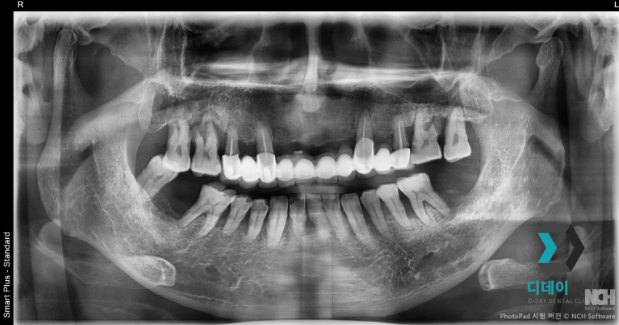

양쪽 위아래 어금니 치주염으로 내원하신 환자분입니다.

양쪽 어금니 심한 치주염으로 인해 발치 후

즉시 임플란트 식립 진행했습니다

2025-07-15